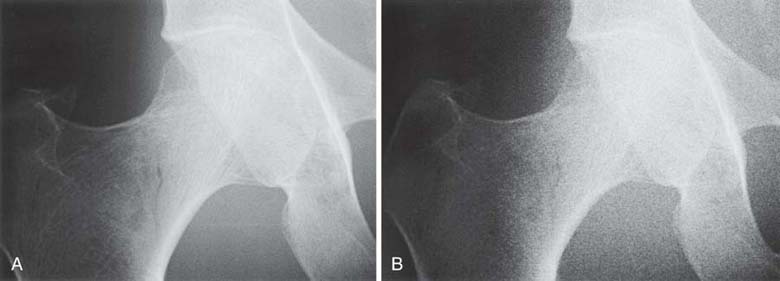

In addition to size distortion, objects that are being imaged can be radiographically misrepresented by distortion of their shape. Shape distortion can radiographically appear in two different ways: elongation or foreshortening. Elongation refers to images of objects that appear longer than the true objects. Foreshortening refers to images that appear shorter than the true objects. Examples of elongation and foreshortening can be seen in Fig. 3-26.

FIG. 3-26 A, No distortion. B, Foreshortened. C, Elongated. (From Mosby's Instructional Radiographic Series: Radiographic Imaging, St. Louis, 1998, Mosby.)